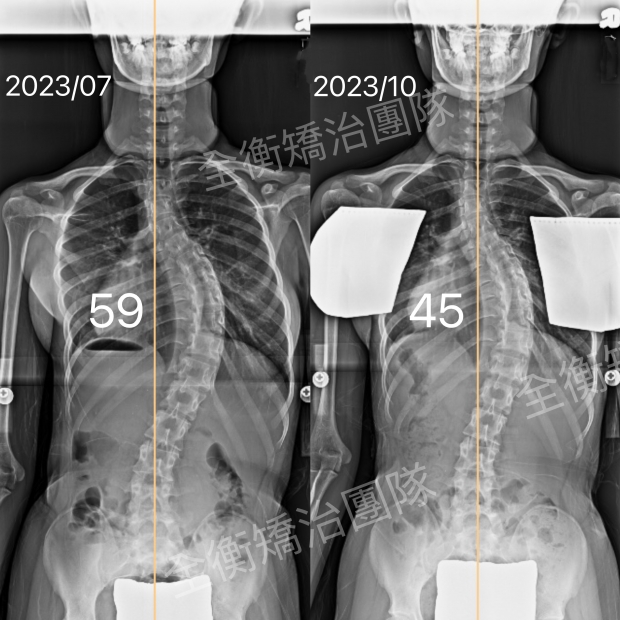

國小六年級女孩,胸椎彎弧 34° ➜ 18°

這位妹妹來到診所時是國小六年級的小朋友,正處於快速成長階段, 經衡觀診所汪作良醫師 專業診斷後, 開始穿戴施羅斯側彎矯治背架並積極學習施羅斯側彎矯治運動,持續追蹤與調整,度數進步 47% ,胸椎側彎角度:34° → 18°